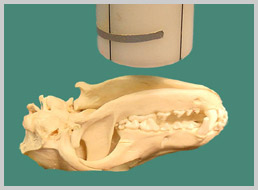

The patient is in dorsal recumbency, with the hard palate parallel

to the film. If possible, the endotracheal tube should be removed

before exposure.

The diagnostic ability of this technique is limited by superimposition

of structures. An intra-oral technique can also be performed with

less superimposition.

Positioning for Ventro-dorsal skull